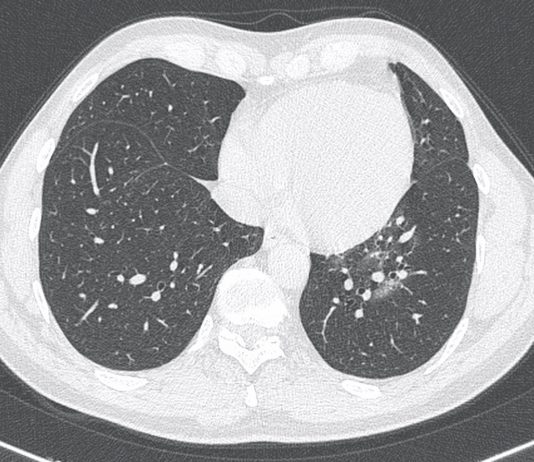

Uomo di 60 anni

Insorgenza di dispnea e febbre

APR: silente